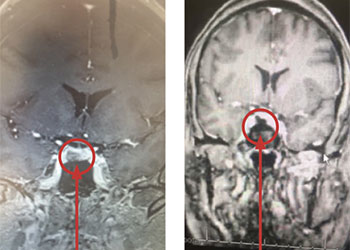

Pineal Region Meningioma

Author: Michael Brisman M.D., F.A.C.S., Read More!

Pituitary Tumor with Cushing’s Disease